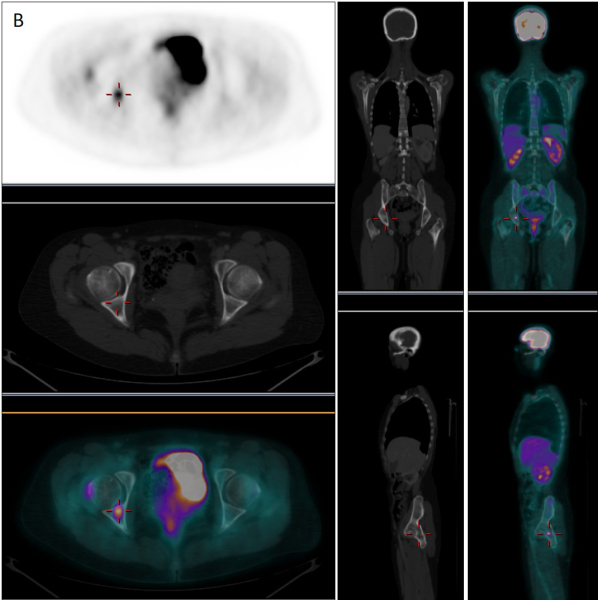

En febrero de 2019, ante la aparición de discreto dolor en cadera derecha y leve aumento del marcador tumoral CA-15-3 (35 U/mL) sospechosos de recaída, se realizó nueva GO que mostró persistencia de lesiones intensamente blásticas a predomino en columna vertebral, sin cambios respecto al estudio realizado 6 años antes (fig. 1-C). Se decidió realizar tomografia por emisión de positrones/TC con fluor-18-desoxi-D-glucosa (18F-FDG-PET/TC) para la caracterización de las lesiones invariables o detectar nuevas localizaciones sugerentes de recidiva. El estudio PET/TC (fig. 2B) demostró la presencia de una nueva lesión ósea intensamente hipermetabólica (SUVmax = 5,35) en región acetabular derecha, sin traducción aparente en la imagen radiológica, muy sugerente de recaída tumoral que justificaba la clínica y la reciente alteración analítica, mientras que el resto de las lesiones basalmente esclerosas e intensamente positivas en la GO resultaban completamente negativas desde el punto de vista metabólico (fig. 2A).

La GO se debe emplear solamente ante la sospecha de progresión, para lo cual se deben documentar al menos dos nuevas lesiones después del período "llamarada" (primeras 12 semanas) con un lapso de al menos 6 semanas(4) y no para valoración rutinaria de respuesta al tratamiento, por el riesgo de interpretación equivocada. Por otro lado, la 18F-FDG-PET/TC mide directamente la actividad metabólica de las células tumorales a través de la captación de glucosa permitiendo caracterizar los hallazgos inespecíficos de la GO, especialmente aquellas lesiones basalmente esclerosas que permanecen positivas en pacientes respondedores.

En el caso que presentamos, la GO permitió detectar correctamente diseminación ósea en el momento del diagnóstico, pero tras un adecuado manejo terapéutico, las lesiones esclerosas en TC continuaron exhibiendo durante años intensa actividad osteogénica, difícilmente interpretable en un contexto de remisión clínica y analítica. Sin embargo, ante una sospecha real de recaída tumoral, el estudio gammagráfico no demostró aparición de nuevas lesiones ni modificación de las previamente existentes. Por su parte, la PET permitió descartar viabilidad tumoral en las lesiones sospechosas en las técnicas de imagen convencional, permitiendo la detección de recaída ósea a través de una nueva lesión hipermetabólica que explicaba la aparición de signos analíticos y clínicos de recidiva.